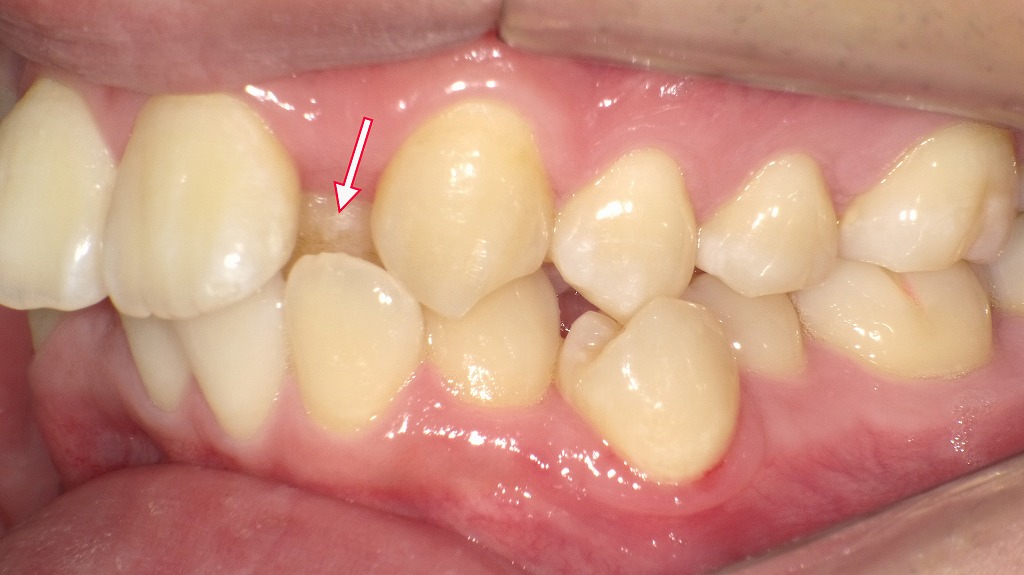

歯そのものの位置や傾きが原因で起こる受け口を「歯槽性(しそうせい)の反対咬合」と呼びます。下記は7歳児の口腔内写真です。矢印の右上1番・2番、左上2番が歯槽性の反対咬合になっています。

下記は成人の口腔内写真です。矢印で示した左上2番の歯が、歯槽性の反対咬合を示しています。